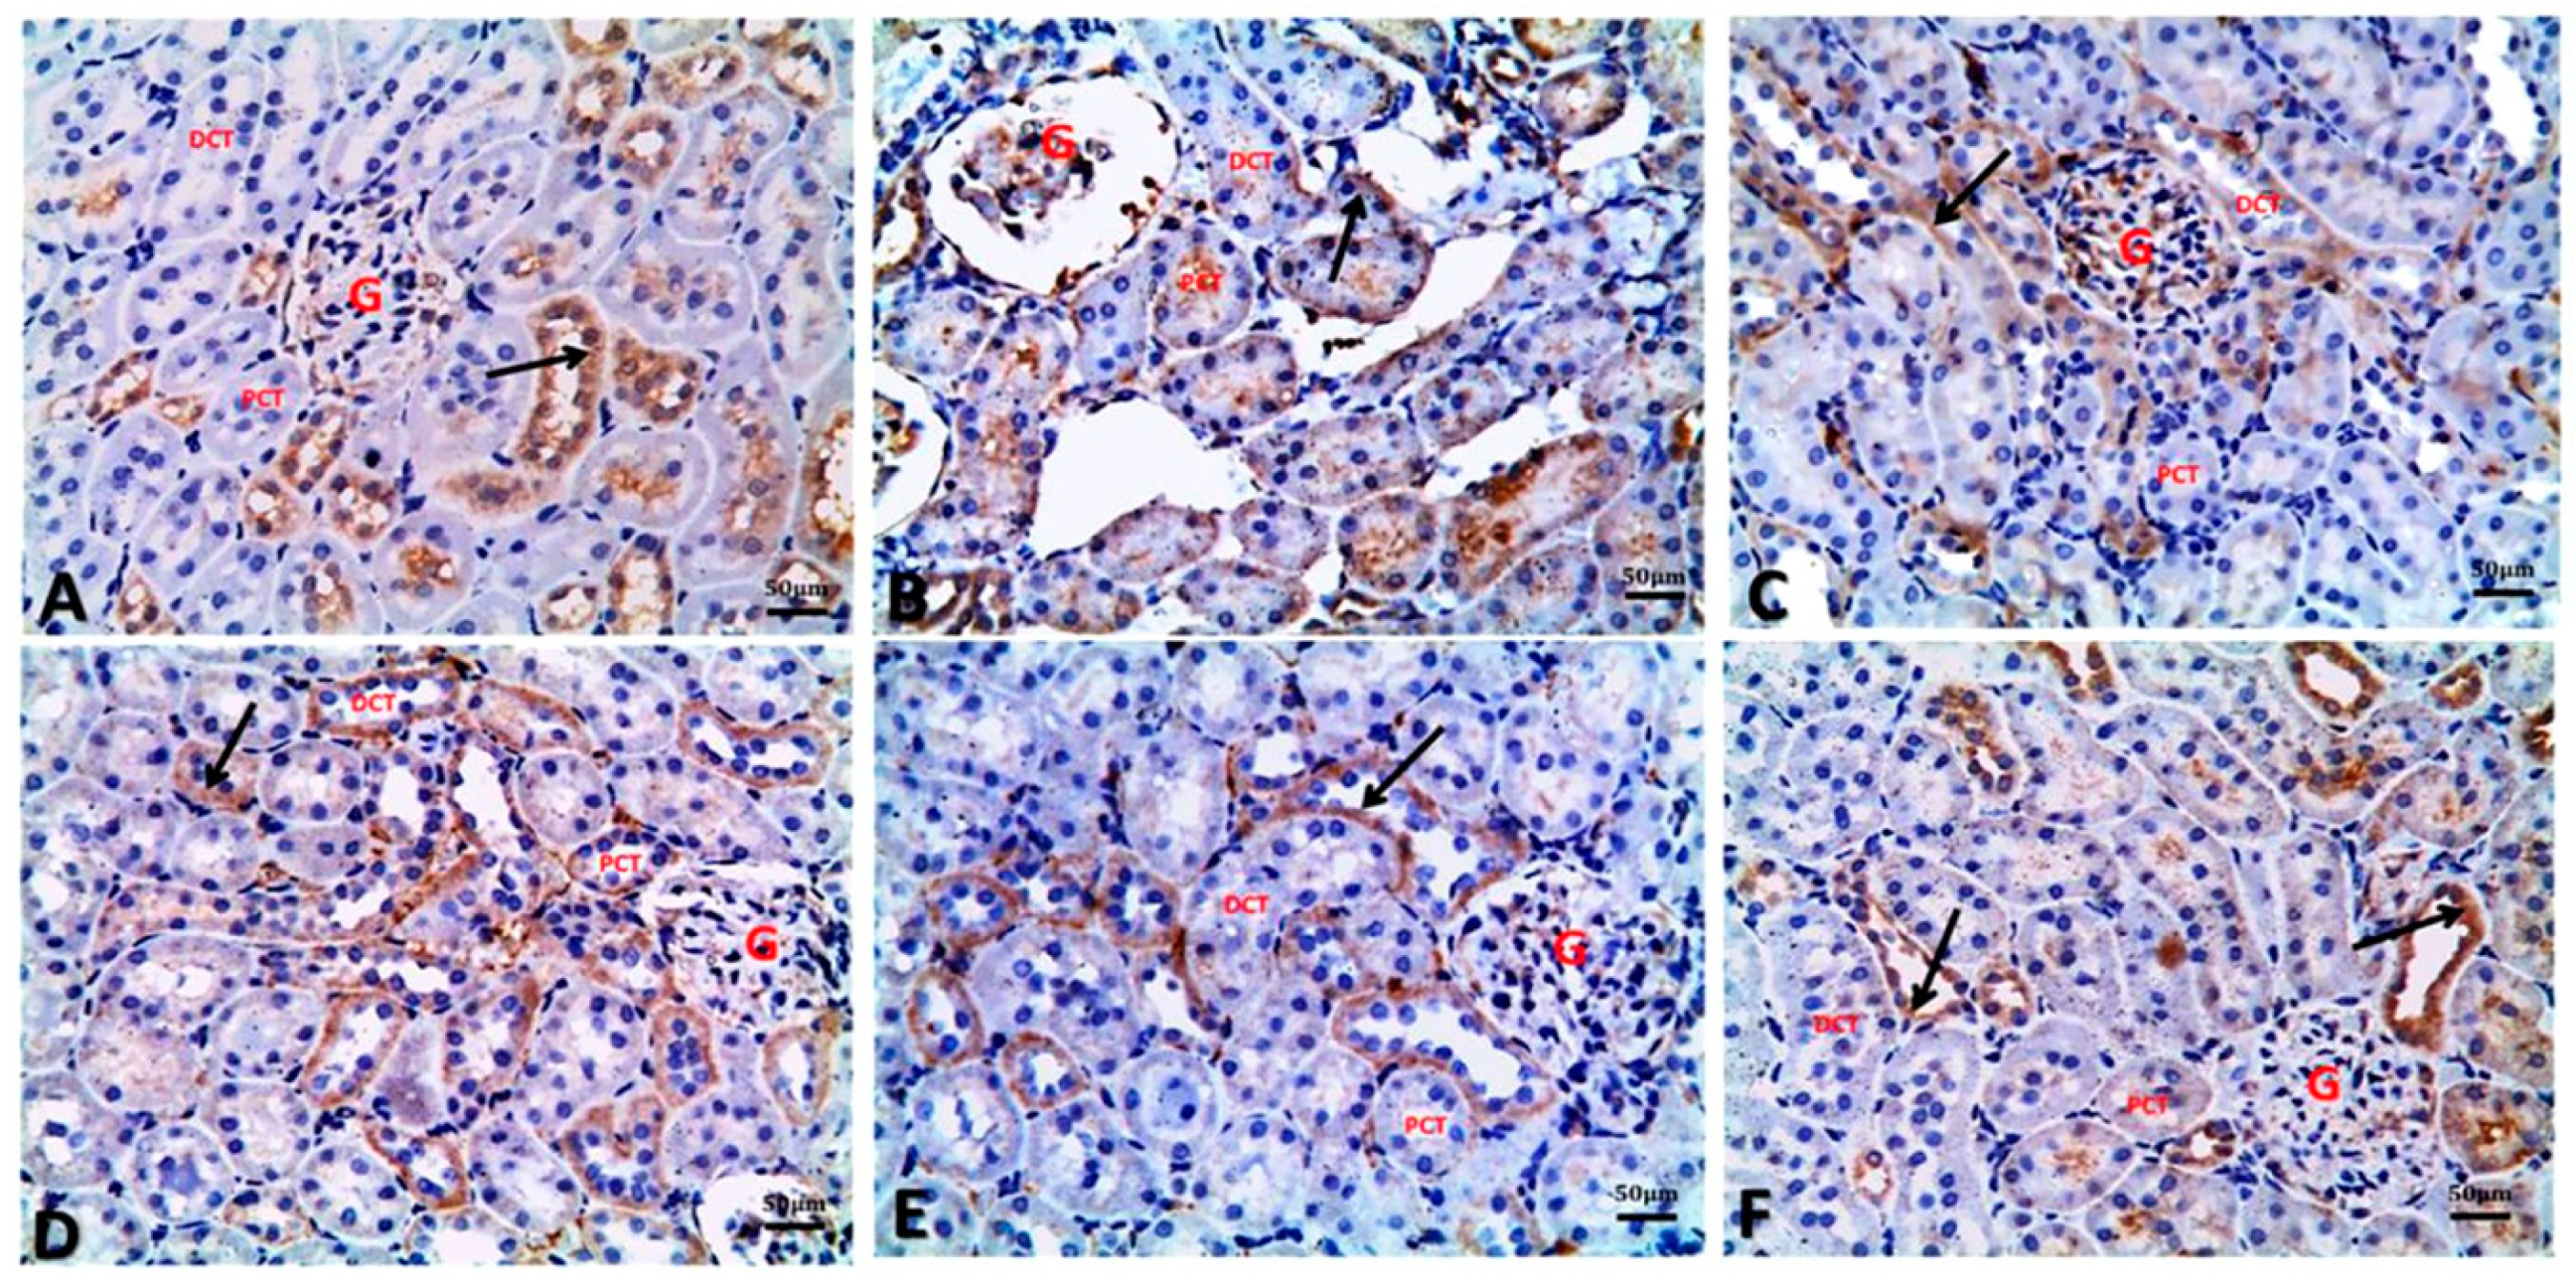

3.7. Argan Oil Modulated Betamethasone-Induced Increase of Bax and Caspase-3 and Decrease of Bcl-2 and PCNA Expressions in Renal Tissues of Rats

| IHC | Experimental Groups | |||||

|---|---|---|---|---|---|---|

| Control | BM | AO/0.5 | AO/1 | BM + AO/0.5 | BM + AO/1 | |

| Bax (% of positive cells/HPF) | 9.85 ± 0.61 c | 28.24 ± 1.43 a | 8.37 ± 0.54 c | 7.25 ± 0.31 c | 15.94 ± 1.01 b | 14.21 ± 1.05 b |

| Bcl-2 (% of positive cells/HPF) | 27.33 ± 0.88 a | 5.36 ± 0.17 b | 24.35 ± 0.54 a | 25.40 ± 0.44 a | 28.67 ± 0.50 a | 28.82 ± 0.13 a |

| Bax/Bcl-2 Ratio (% of positive cells/HPF) | 0.36 ± 0.06 b | 5.27 ± 0.73 a | 0.34 ± 0.02 b | 0.29 ± 0.03 b | 0.56 ± 0.03 b | 0.49 ± 0.02 b |

| Caspase-3 (% of positive cells/HPF) | 7.07 ± 0.72 c | 39.87 ± 2.00 a | 6.42 ± 0.36 c | 5.49 ± 0.64 c | 18.48 ± 1.73 b | 15.75 ± 1.92 b |

| PCNA (% of positive cells/HPF) | 32.75 ± 0.39 a | 10.67 ± 0.36 b | 33.35 ± 0.49 a | 34.13 ± 0.46 a | 30.48 ± 0.43 a | 31.70 ± 0.31 a |